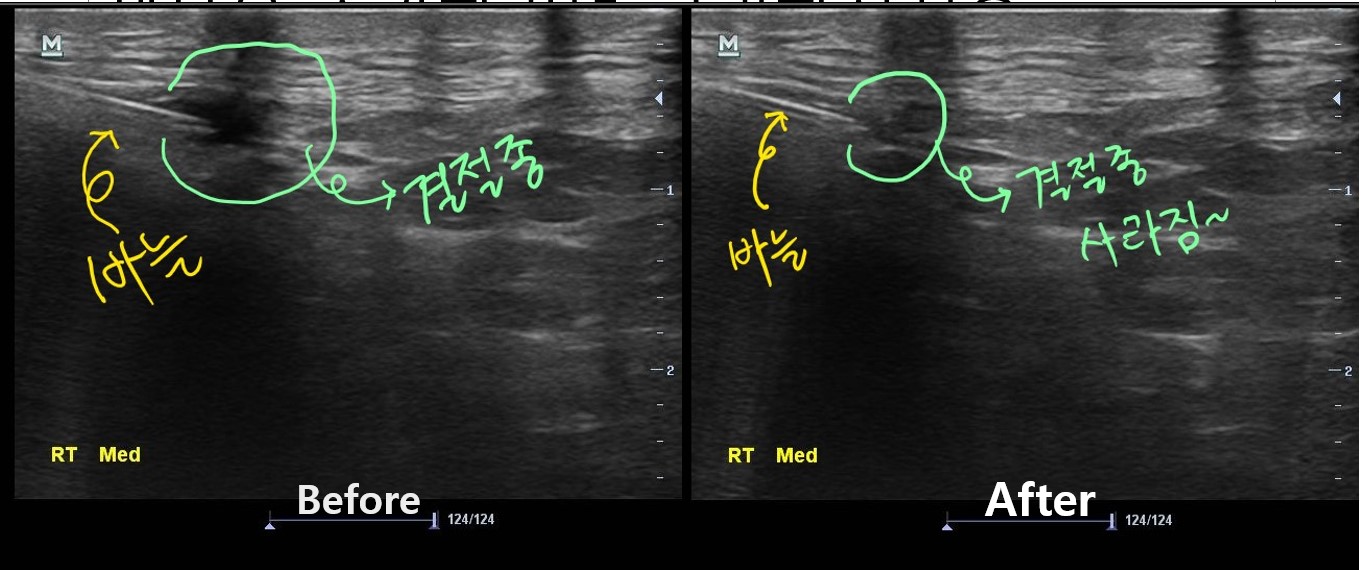

나 : 내측반월판 연골 부위에 물혹이 하나 생겨있습니다.

나 : 네 결절종이라고 하는 건데요... 무릎을 굽히실때 이게 주변 조직을 누르면서 통증이 발생한듯 합니다.

치료 후 3개월이 지난 현재, 이 환자분은 다행히 물혹이 재발되지 않아 큰 불편함없이 잘 지내고 있습니다. 아직 더 지켜보긴 해야 하지만요...